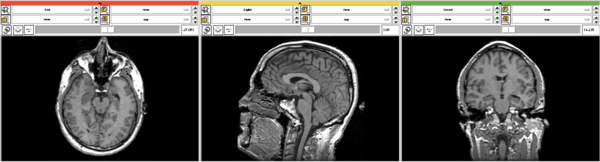

For the following example an image dataset of a human head was used.

After execution of the privacy module there is a additional surface visible on the front of the head surface.

This example shows the data in the 3D view in slicer before and after the usage of two different parameter settings in the module.